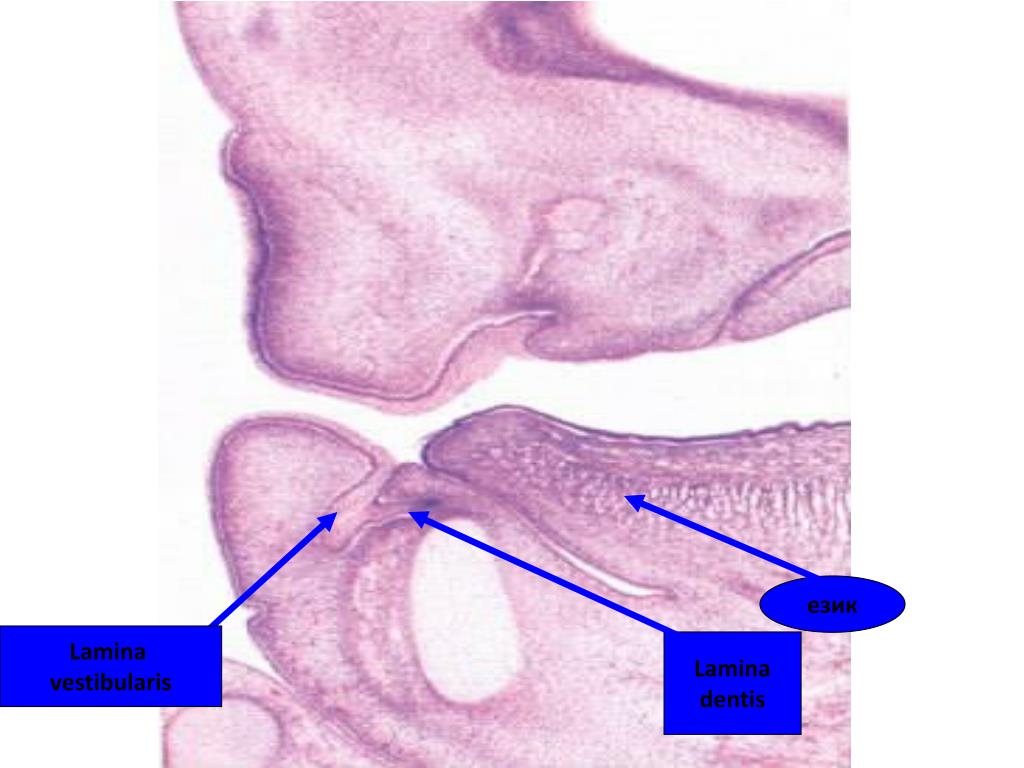

14. език Lamina vestibularis Lamina dentis

13. Lamina dentis , Lamina vestibularis • Вестибуларна пролиферация-lamina vestibularis; • Орална пролиферация- lamina dentis. Lamina dentis Lamina vestibularis

12. Образуване на вестибулума от развитието на L. vestibularis